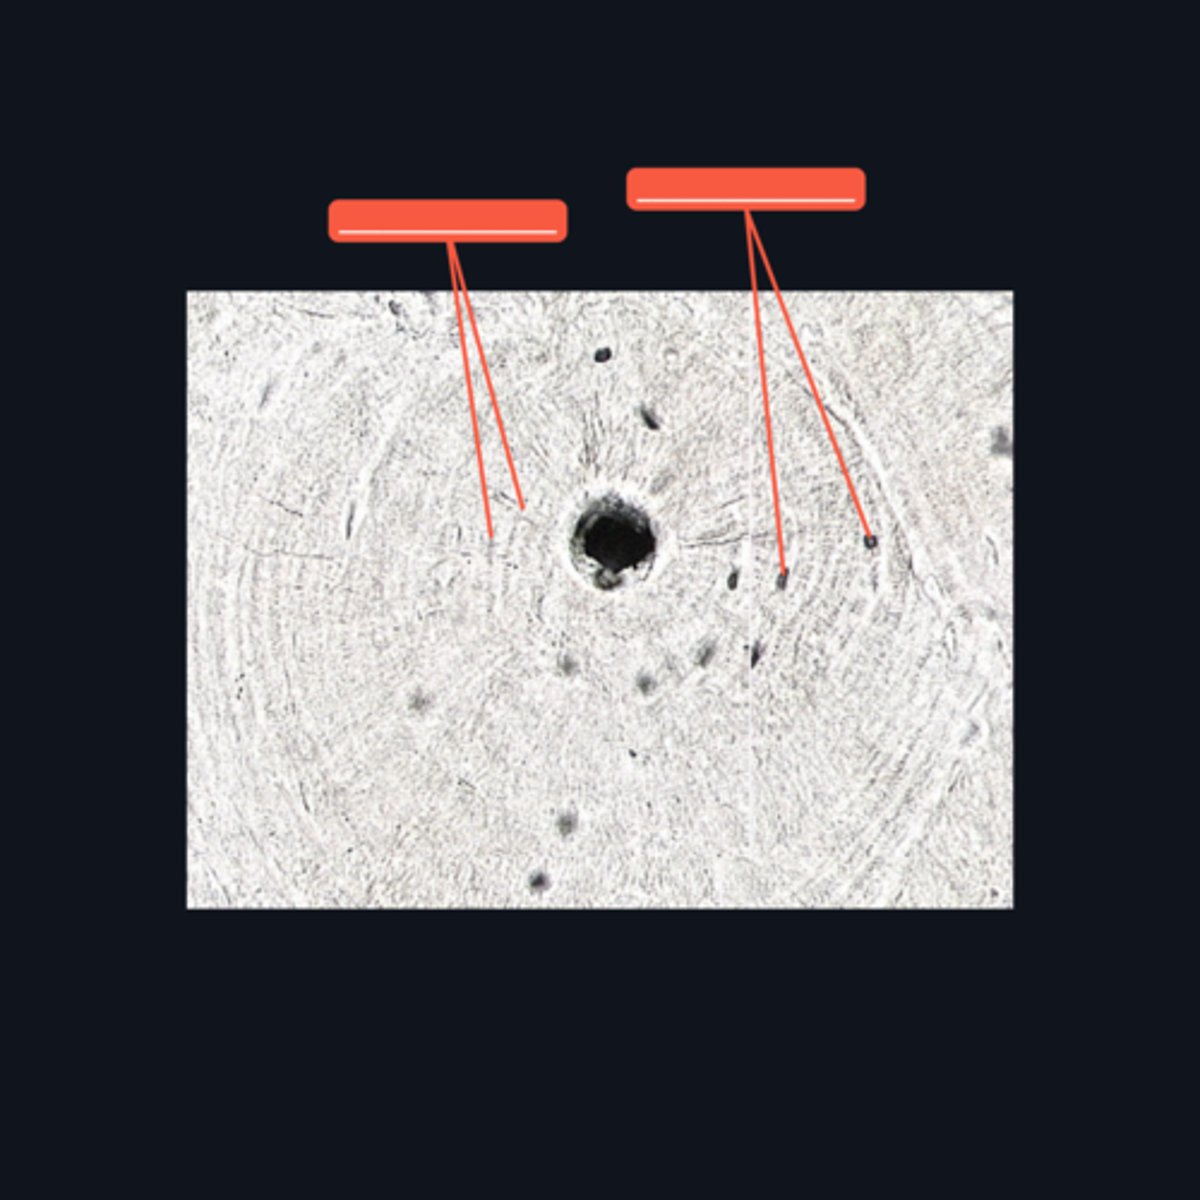

Osteoblast

Identify structure A

Osteoprogenitor cells

Identify structure B

Diaphysis; shaft

Identify what part of a typical long bone is encompassed by the bracket symbol. It is also known as the _____ of a long bone.

Medullary cavity

Identify the area encompassed by the bracket symbol, which is a hollow core that contains the developing blood cells and spongy bone spicules.

Proximal epiphysis; hyaline cartilage

Identify what part of a typical long bone is encompassed by the bracket symbol. What type of cartilage is it made up of?